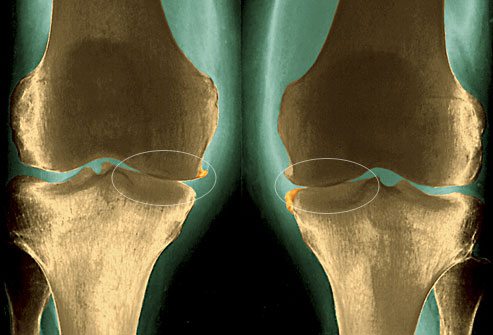

Дегенеративно-дистрофическое заболевание, опасное рецидивирующим течением. В отличие от артрита не сопровождается воспалительным процессом в коленном суставе. По мере развития остеоартроза разрушаются хрящевые ткани, которые выстилают костные головки, обеспечивают гладкость их скольжения. Для стабилизации сустава патологически разрастаются костные пластинки, формируются остеофиты. Они сдавливают мягкие ткани, связки и сухожилия, запуская воспалительный процесс. На этой стадии возникают первые клинические проявления — утренняя припухлость, скованность движений, боль, усиливающаяся при подъеме тяжелых предметом.